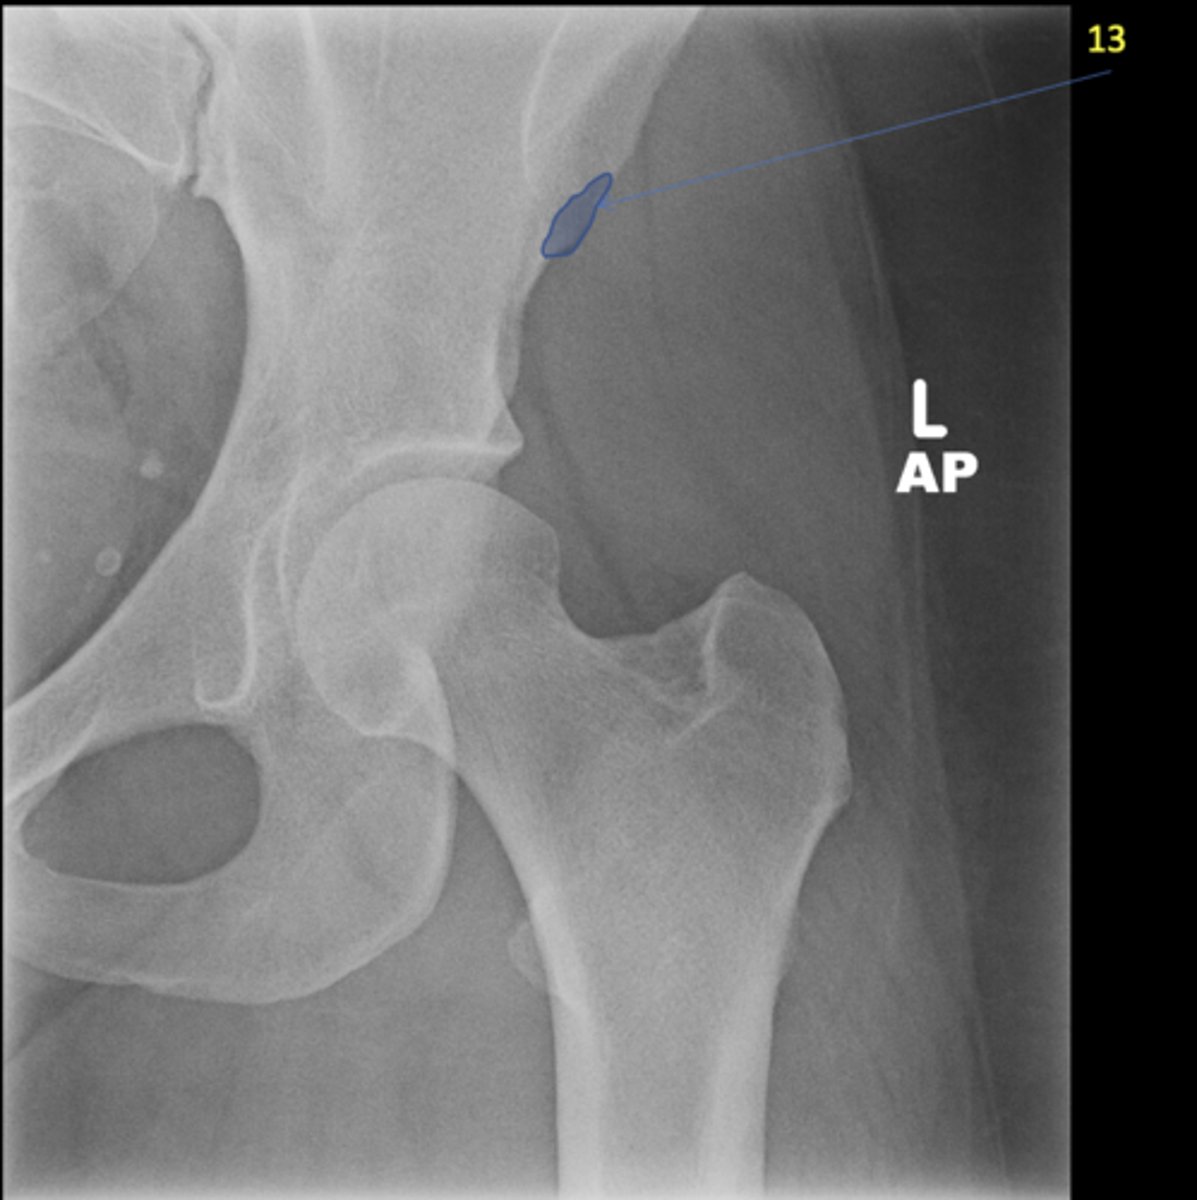

Left AP hip

View?

Phleboliths

ID 1

Obturator foramen

ID 2

Kohler's teardrop

ID 3

Gluteus medius

ID 4

Ischial tuberosity

ID 5

Acetabulum

ID 6

Anterior inferior iliac spine

ID 8

Lesser trochanter

Greater trochanter

ID 9

Sacroiliac joint

ID 10 (joint)

Sacrum

ID 11 (bone)

ID 12

Anterior superior iliac spine

ID 13